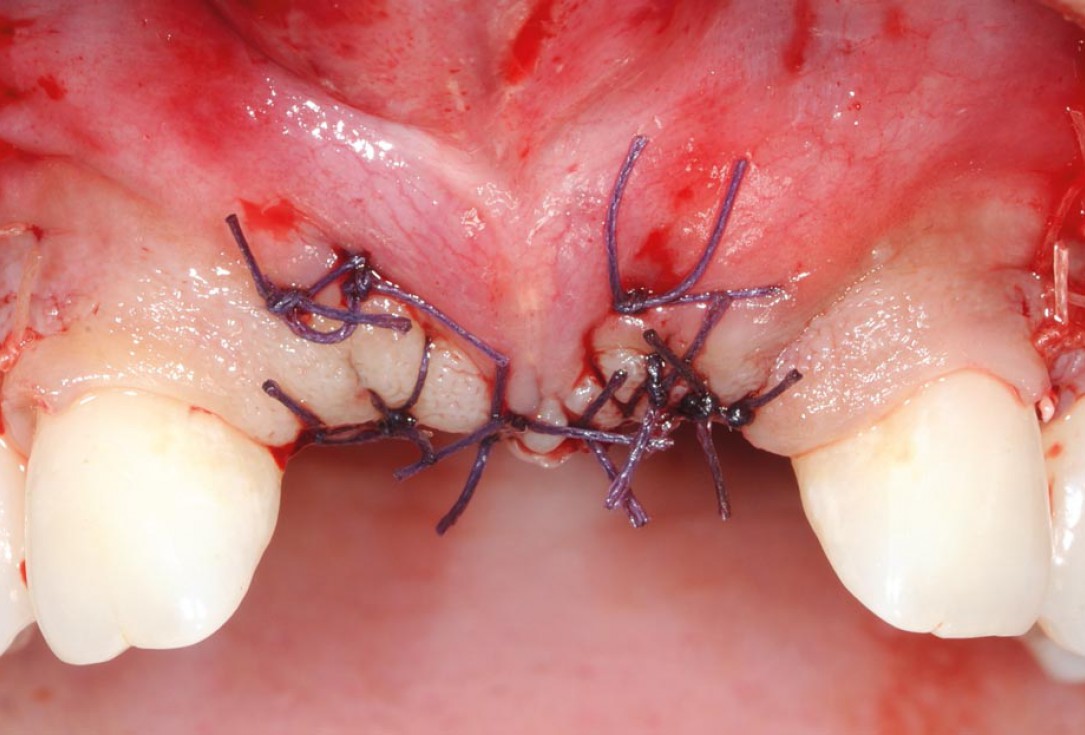

17/26 - Mattress sutures to stabilize the graftBone augmentation in aesthetic zone with maxgraft® bonering - Dr. A. Patel

18/26 - Sutured free of tension with vycrilBone augmentation in aesthetic zone with maxgraft® bonering - Dr. A. Patel